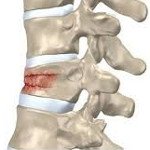

• Компрессионный перелом. Сопровождается сдавлением, раздроблением и клиновидным сплющиванием переднего отдела позвонка. Выделяют три степени компрессии: 1 степень – уменьшение высоты тела на 1/3 или менее, 2 степень – уменьшение высоты тела на 1/3-1/2, 3 степень – уменьшение высоты тела на 1/2 или более. Чаще страдает один позвонок, реже наблюдается повреждение нескольких соседних позвонков. Дужки, суставные отростки и межпозвонковые диски при таких переломах не страдают. Подобные повреждения часто возникают при падениях с высоты, при падении на ноги возможно сочетание с переломом пяточных костей, при падении на ягодицы – с переломом таза.

Позвоночник состоит из отдельных костей – позвонков, соединенных между собой связками, хрящами и мелкими суставами. Каждый позвонок образован обращенным вперед телом и обращенной назад дугой. В пространстве между задней поверхностью тела и передней поверхностью дуги находится спинной мозг. В норме тело позвонка имеет цилиндрическую форму, высота его переднего и заднего отделов примерно одинакова. При компрессионном переломе передние отделы позвонка сдавливаются, и он принимает клиновидную форму. Повреждение может возникать в любом отделе позвоночника, однако чаще всего страдает переходный отдел (нижние грудные и верхние поясничные позвонки).

С учетом изменения высоты позвонка различают 3 степени переломов:

• 1 степень – уменьшение высоты позвонка менее чем на треть.

• 2 степень – уменьшение высоты позвонка менее чем на половину.

• 3 степень – уменьшение высоты позвонка более чем на половину.